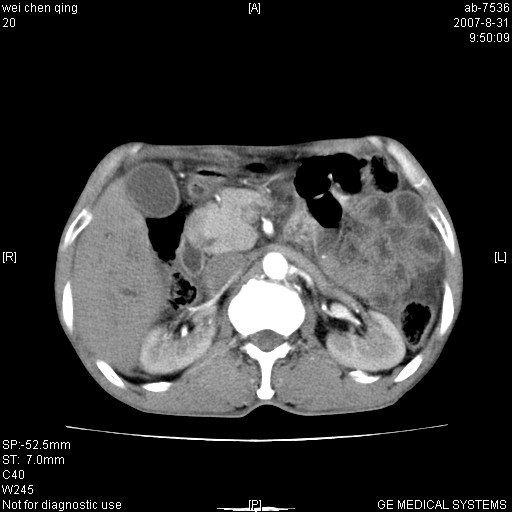

以下是引用zyyzzy在2007-8-31 14:34:00的发言:[br]该病人肝内胆管扩张,胆囊及胆总管未见明显扩张。在倒数第9层图像上可看到左右肝管结合部(肝总管)有软组织影,此处应薄层扫描。考虑肝总管占位(ca)、腹水。[br]